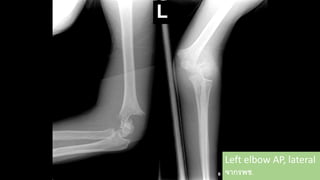

Left elbow

AP, lateral

Totally displacement

Closed fracture of left supracondyle

Gartland III

Left elbow AP,lateral จากรพช.